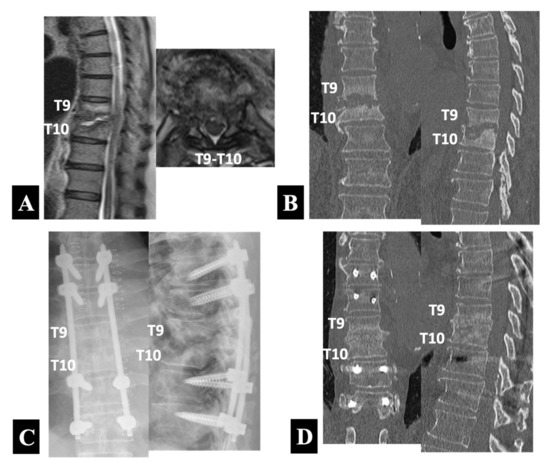

- Case 2 in Group 2-A (Figure 4):